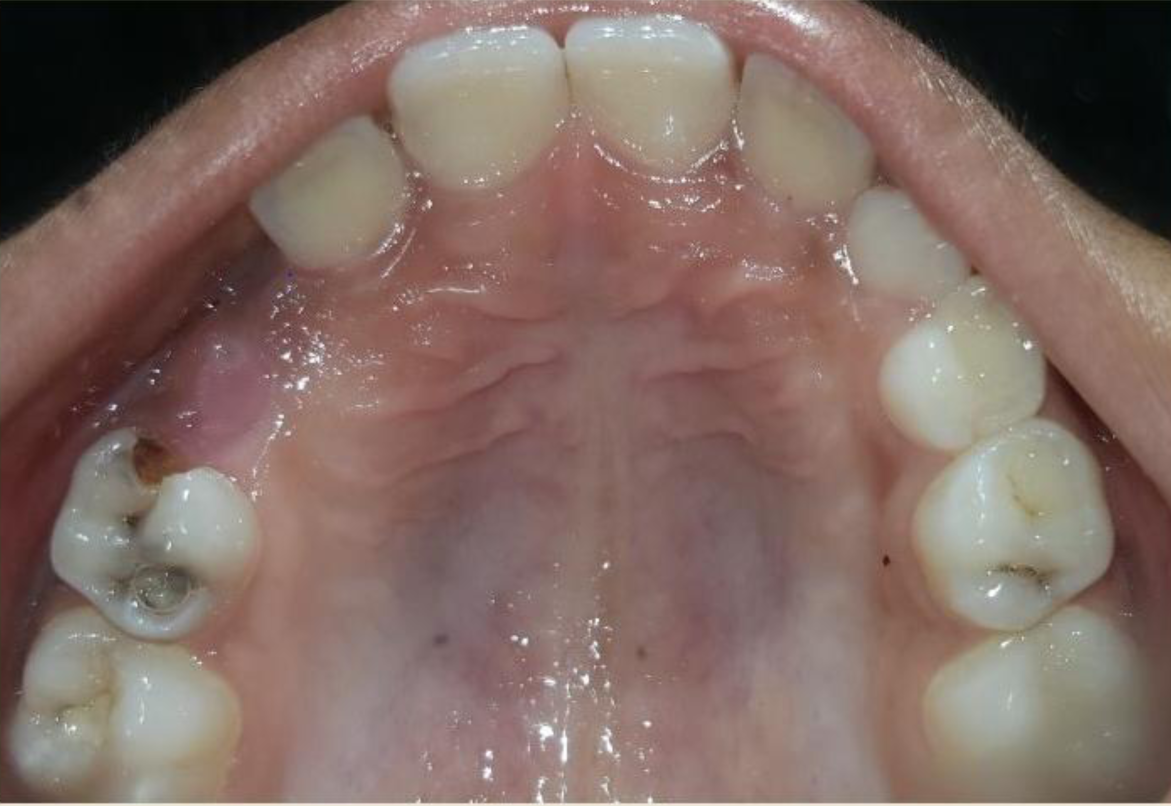

A nine year old boy reported to the Department of Pedodontics and Preventive Dentistry of Bharati Vidyapeeth Deemed University, Sangli with a chief complaint of pain and abscess in the lower left back region of the jaw since one month. Patient was a known case of autism spectrum disorder. He was inattentive, hyperactive and showed repetition of gestures. Psychological testing report showed childhood autism rating scale (CARS) 2, which falls into mild to moderate autistic category. Vineland social maturity scale (VSMS) measuring the social intelligence of child was found to be 31.5 with social age of around 5-6years. The family history was non-contributory. He was not on any medications and had reported no history of drug allergies. Extra-oral examination showed no specific findings (Figure 1). Intraoral examination revealed multiple carious lesions (Figure 2) (Figure 3). Occlusal caries involving enamel, dentin and pulp with 55 and 75. Intra oral dentoalveolar abscess was also seen in relation with 75 (Figure 4). Dentinal caries was seen with 85 and occlusal pit and fissure caries was seen with 65. No soft tissue abnormalities were appreciated. Radiographic evaluation by orthopantomogram was also done which revealed no abnormality (Figure 5). It was difficult for the patient to co-operate on the dental chair and understand the instructions given to him; hence treatment was planned under general anaesthesia. A complete pre anaesthetic evaluation was done and the patient was categorized under ASA II. Treatment plan was explained to the child’s parents and a written consent was obtained from them. The dental treatment done under general anaesthesia included pulpectomy of 55, 75 with glass ionomer cement restoration followed by placement of pre trimmed and pre contoured stainless steel crowns (Figure 6) (Figure 7). Glass ionomer cement restorations were done in 65 and 85 and pit and fissure sealants application on 16, 26, 36 and 46. Post-operative orthopantomogram showed well placed restorations and crowns (Figure 8). Patient’s post-operative recovery was uneventful. Treatment rendered reduced the pain and discomfort.Oral hygiene care instructions were given to the parents and maintenance protocol was explained and they were also encouraged for regular follow-up for preventive dental care. The two months follow-up revealed improved eating habits of the child.

Figure 2 Intra oral pre-operative image of the maxilla.